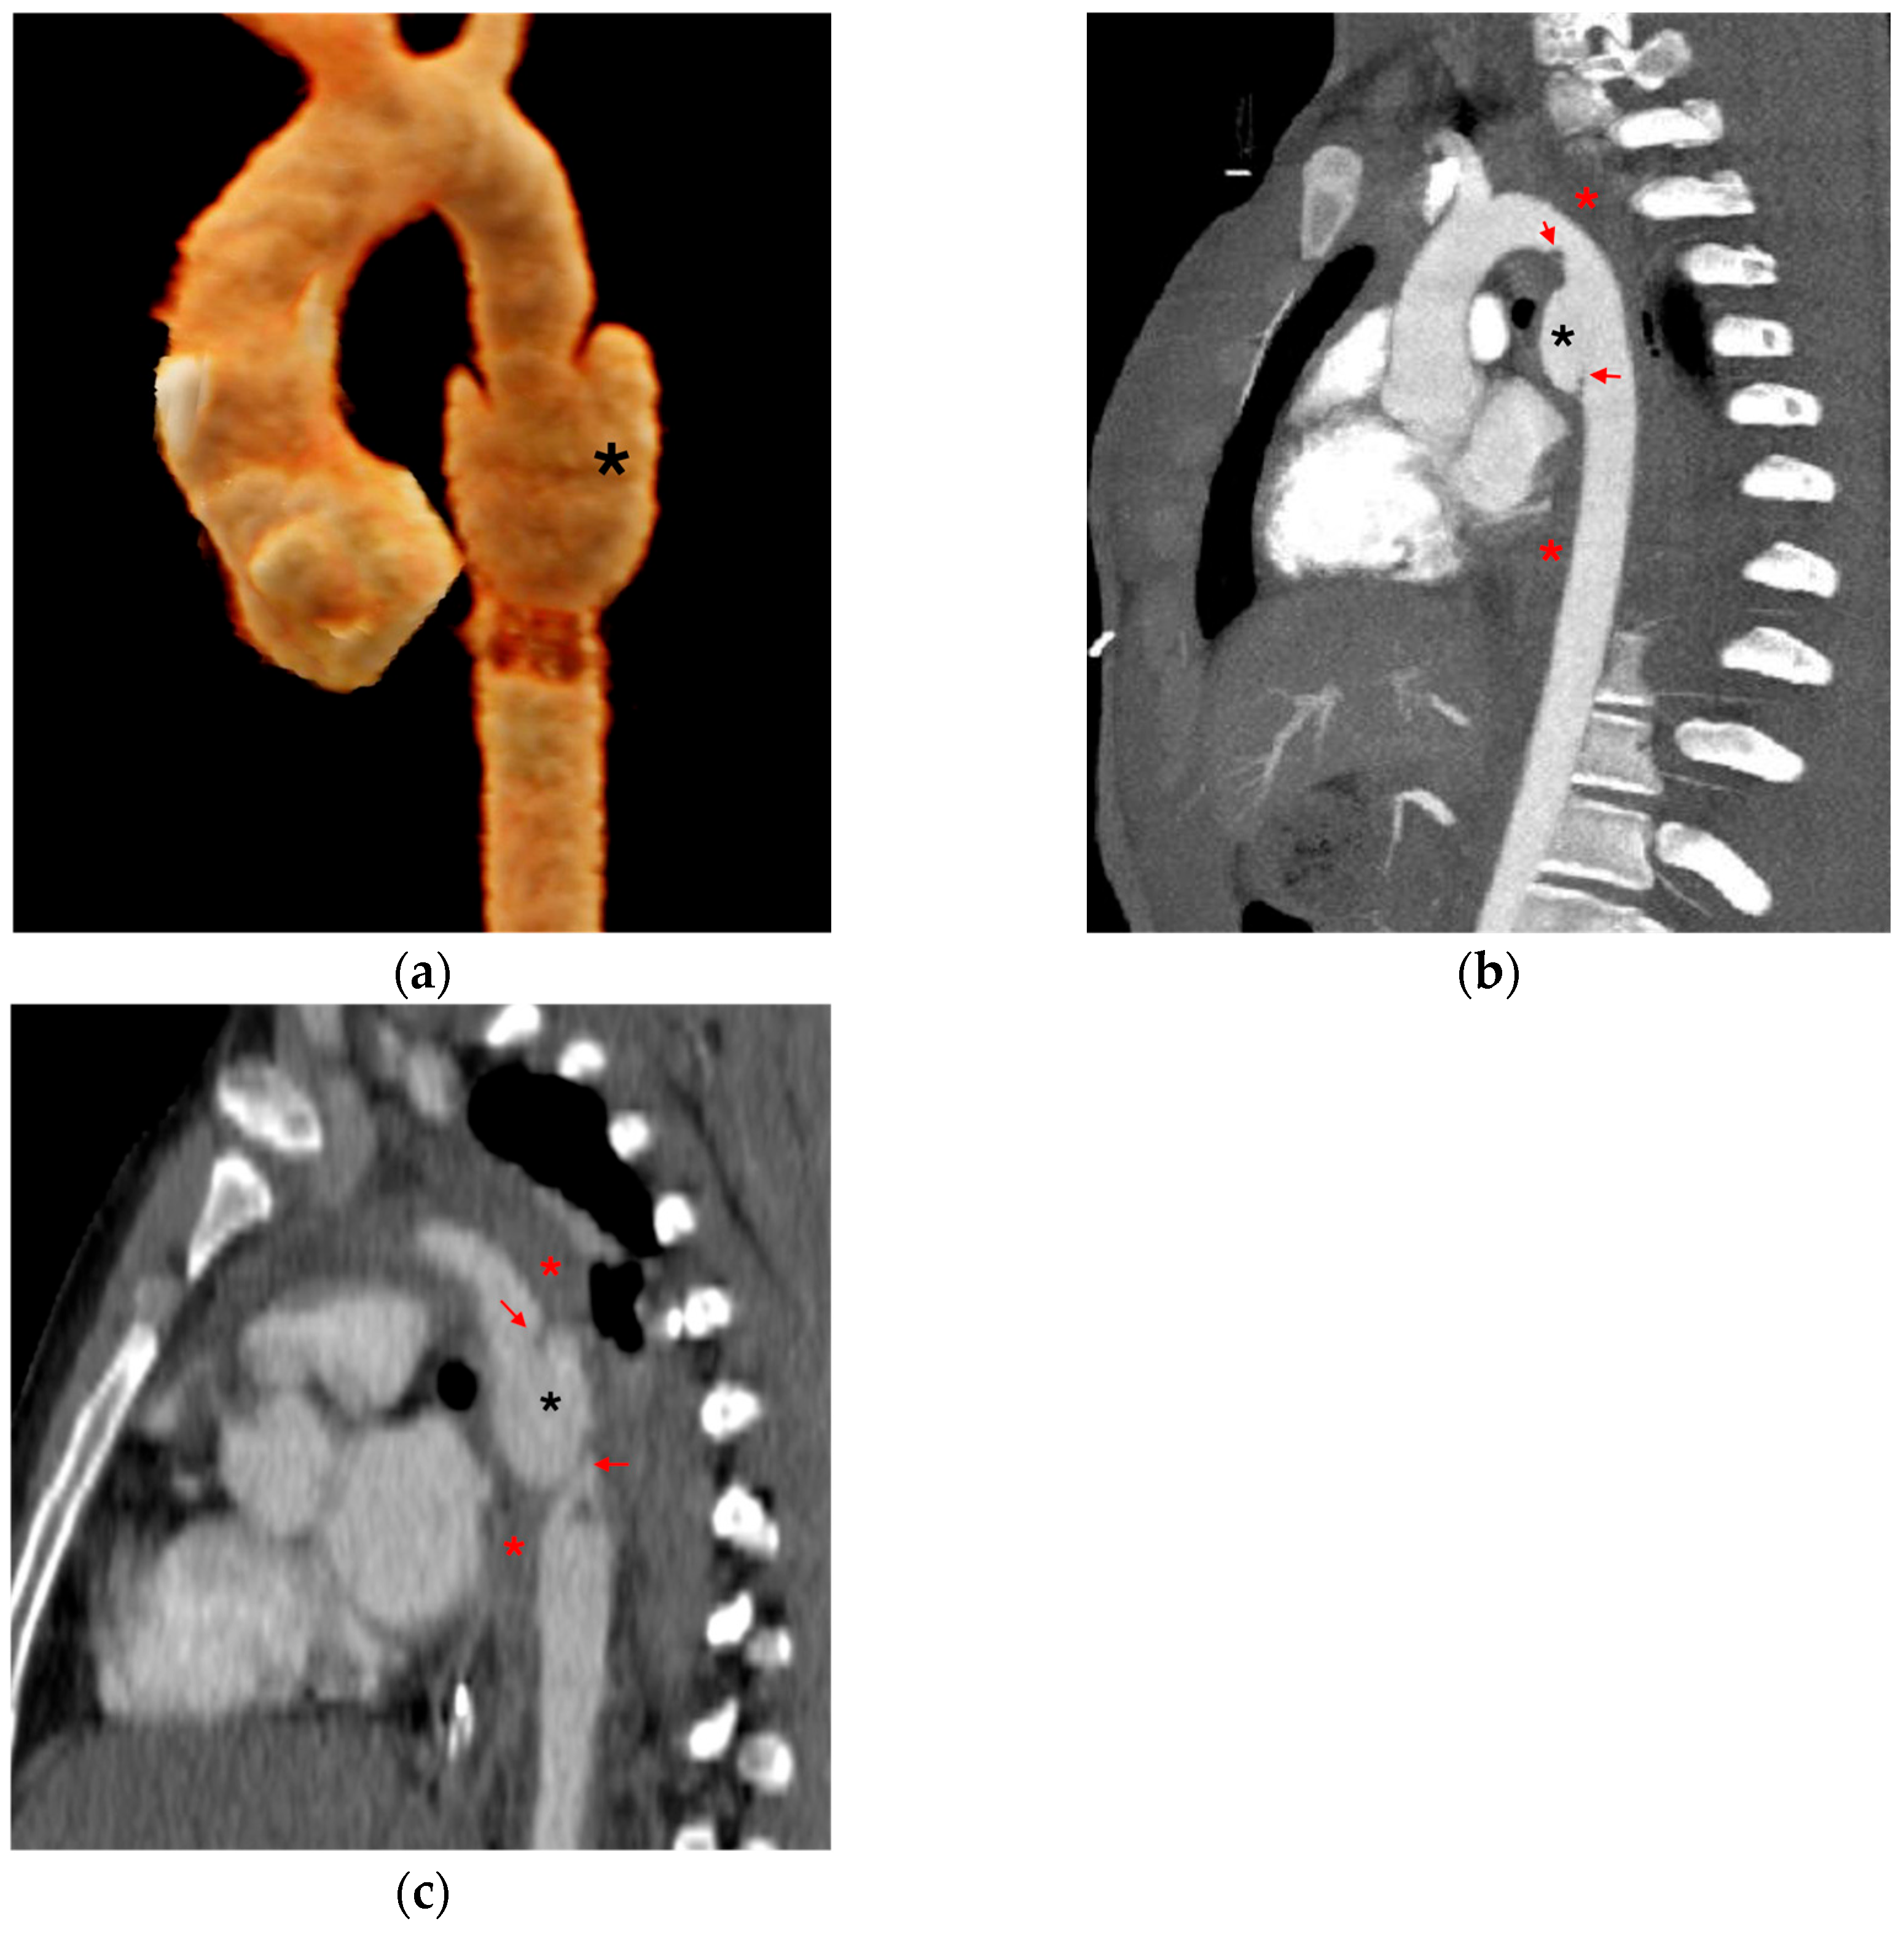

3.1.1. Direct Signs of Aortic Injury

3.1.2. Indirect Signs of Aortic Injury

3.1.3. Mimics and Anatomic Variations